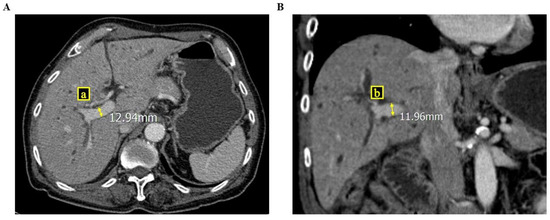

2.2. RPVA/LPVA